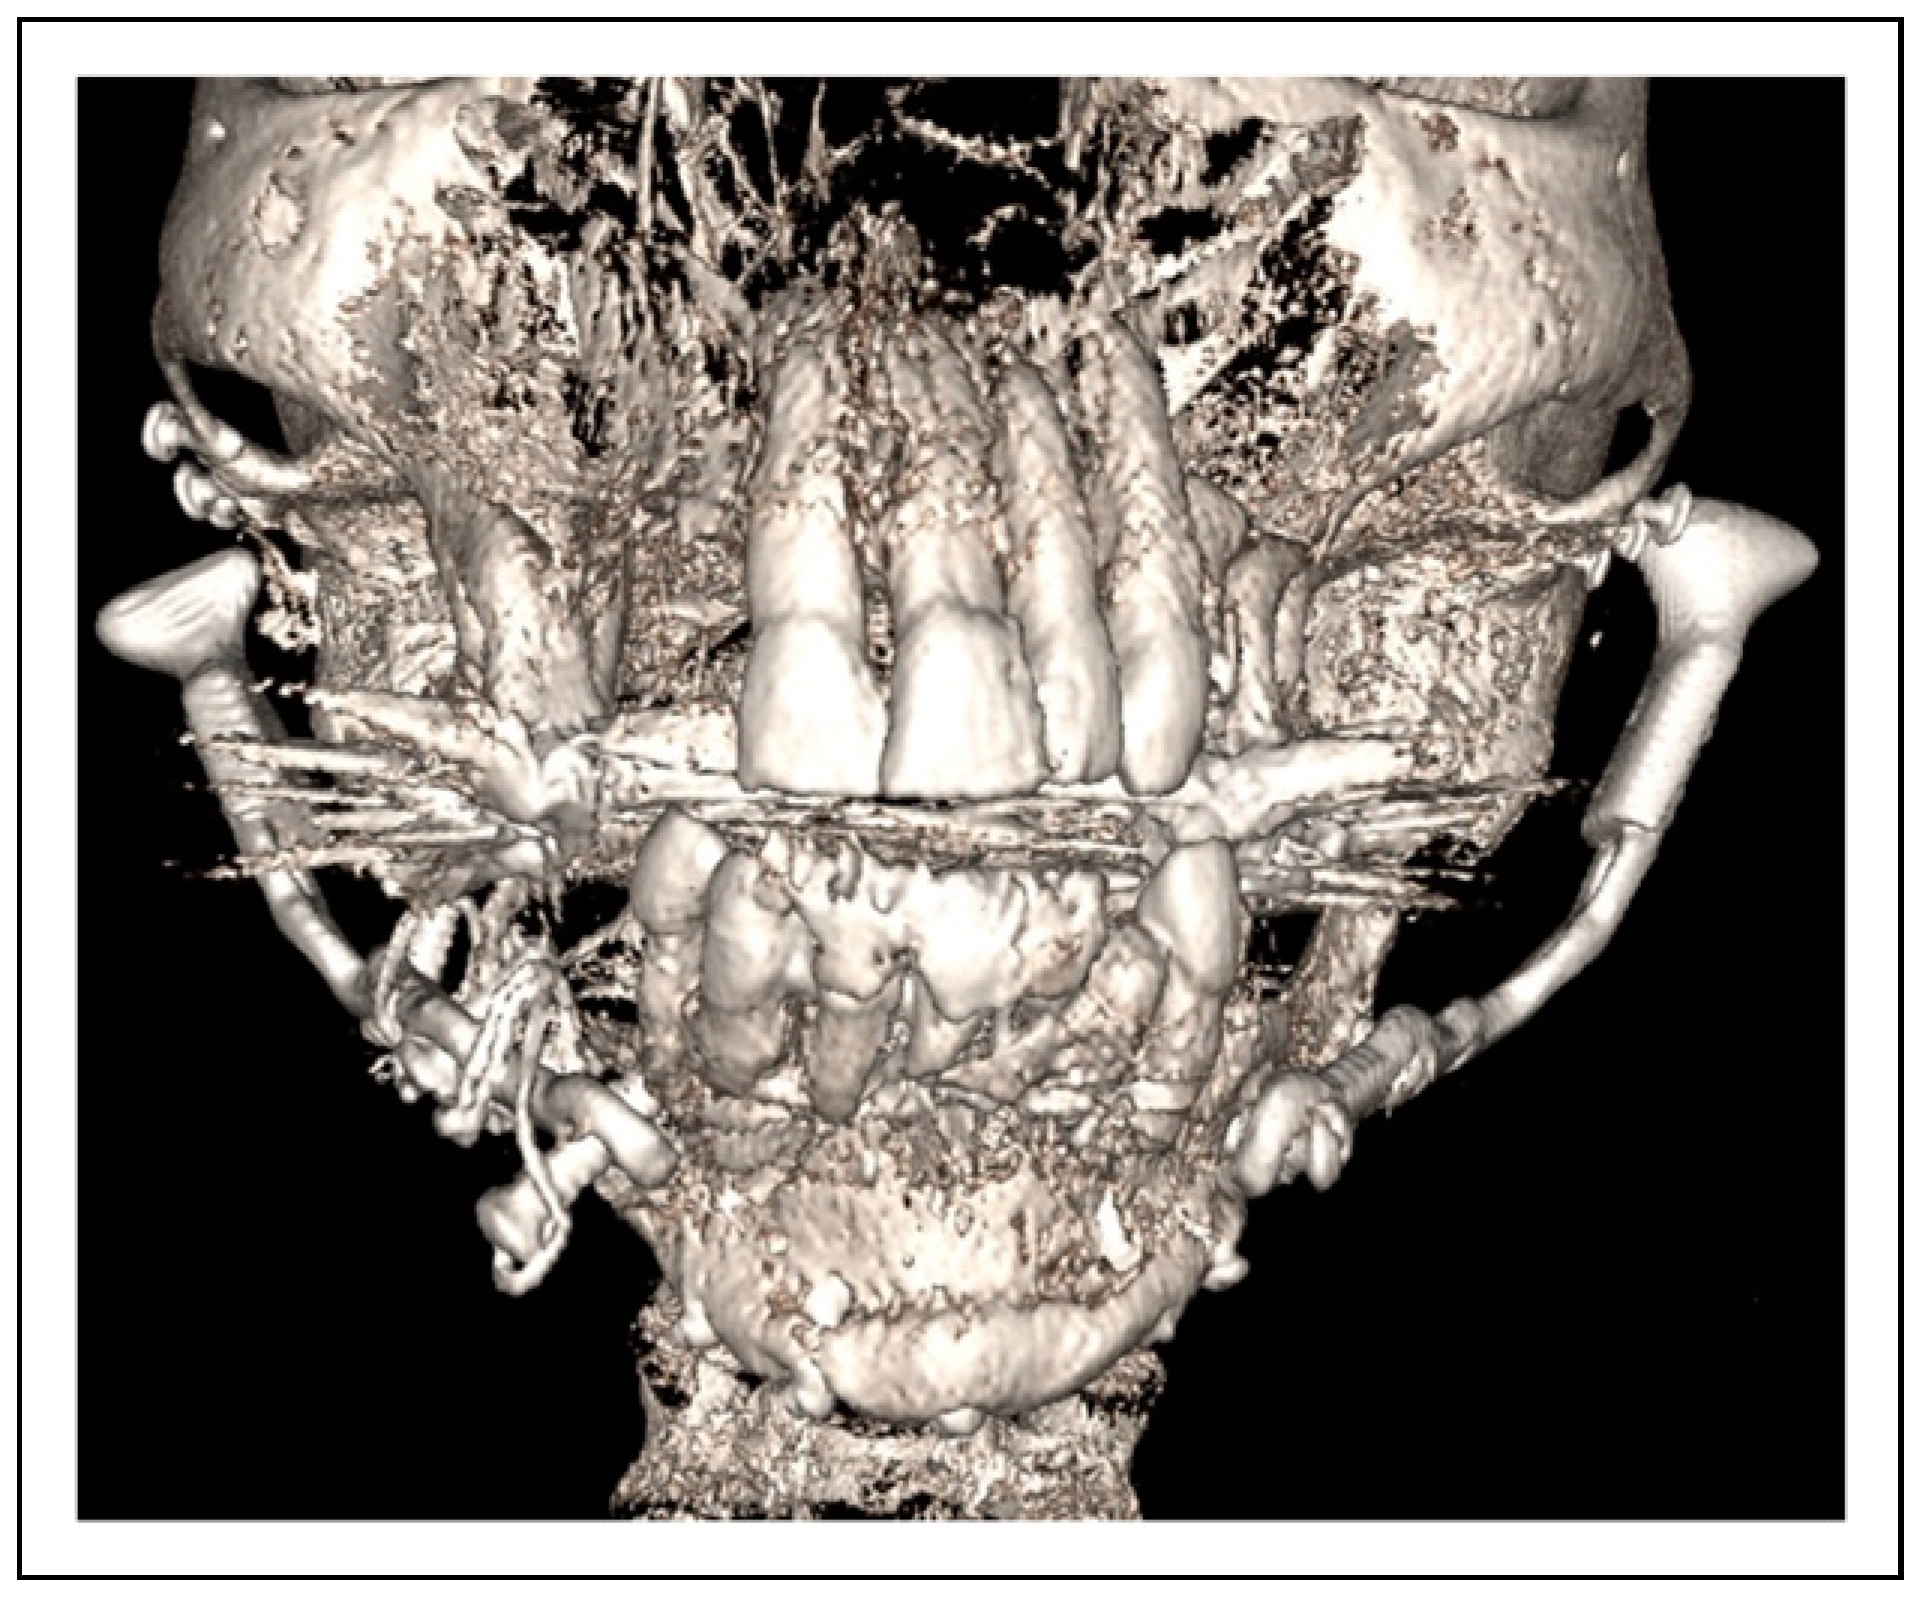

Bilateral TMJ Replacement With Complete Replacement of the Mandible, Patient 8